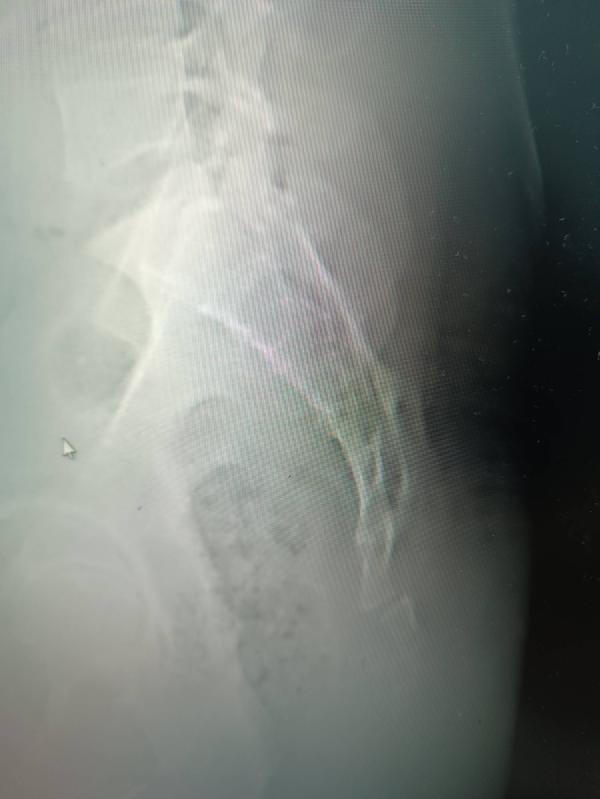

У мужа перелом копчика...

Ходили к двум врачам, сказали месяц ждать...

Если боль не пройдёт то можно оперировать...